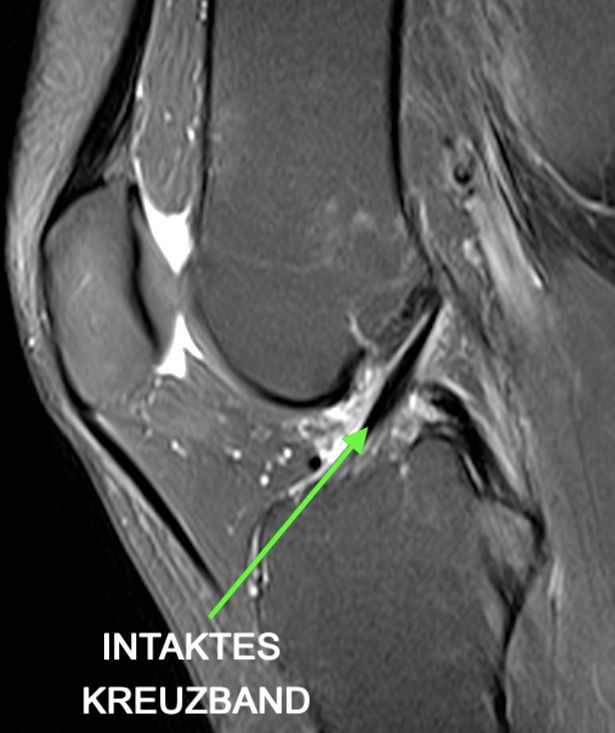

Normalerweise verläuft das vordere Kreuzband gestreckt und parallel zur Blumensaatlinie, die dem Dach des Sulcus intercondylaris entspricht, und weist im Querschnitt eine ovale Form auf. Nach der MRT des Kreuzbandrisses findet ein abschließendes Gespräch mit einem Radiologen statt, der die Aufnahmen auswertet, Ihnen die Ergebnisse erklärt und die passenden Therapiemaßnahmen vorschlägt. Die Vorteile des MRT bei Knieverletzungen Der Vorteil des MRT liegt in der Präzisierung der Diagnose und vor allem der Fahndung nach eventuellen Begleitverletzungen

Kreuzbandriss MRT » Ablauf & Bilder Radiologie ARISTRA. Bei einer MRT-Untersuchung können vor allem die Kreuzbänder sehr genau dargestellt werden Deshalb eignet sich ein MRT sehr gut, um einen Kreuzbandriss zu erkennen